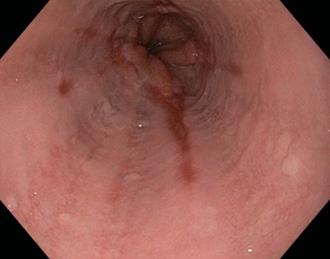

Figura 3. Esófago de Barrett. Metaplasia intestinal de la mucosa esofágica inducida por reflujo crónico. Epitelio poliestratificado plano → monoestratificado cilíndrico intestinal (células caliciformes)(ENAM 2012) Figura 4. Factor anatómico asociado a ERGE es la hernia del hiato tipo I (hernia por deslizamiento)

Esófago de Barrett

Metaplasia intestinal de la mucosa esofágica inducida por reflujo crónico

♦Epitelio poliestratificado plano → monoestratificado cilíndrico

♦La zona de transformación fisiológica (línea Z) entre el epitelio escamoso y columnar se desplaza hacia arriba.

Lesión premaligna que requiere una estrecha vigilancia.

♦Metaplasia → displasia → adenocarcinoma (ENAM 2020)

Incidencia: hasta el 15% de los pacientes con ERGE(ENAM 2010)

Diagnóstico: endoscopía + biopsia

Clasificación:

♦ Segmento corto (< 3 cm)

♦ Segmento largo (> 3 cm) → mayor riesgo de cáncer (adenocarcinoma)

Figura 6. Esofagitis erosiva. Son visibles múltiples Figura 7. Esófago de Barret es una lesión premalgina. Metaplasia → displasia → adenocarcinoma (tercio inferior del esófago) (ENAM 2020)

Figura 8. Esófago de Barrett. El reflujo crónico → el ácido del estómago daña el epitelio escamoso estratificado del esófago distal → que luego se reemplaza por epitelio columnar y células caliciformes.